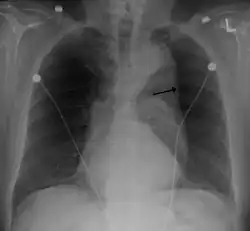

Thoracic aortic aneurysm with arrow marking the lateral border of the aorta